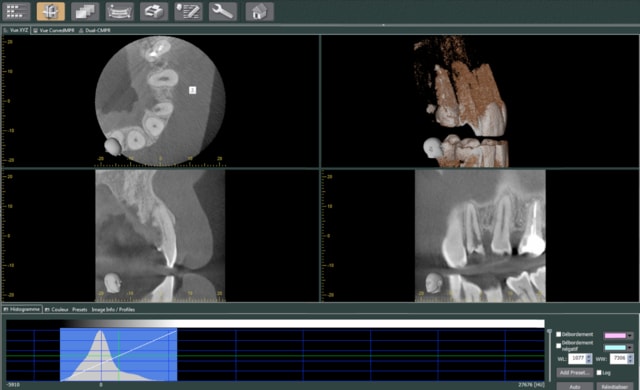

resorption interne.

extraction curetage, pose d'un bloc biobank cortico-spongieux et poudre d'os biobank, membrane at collagene et patch palatin pour fermer le lambeau.